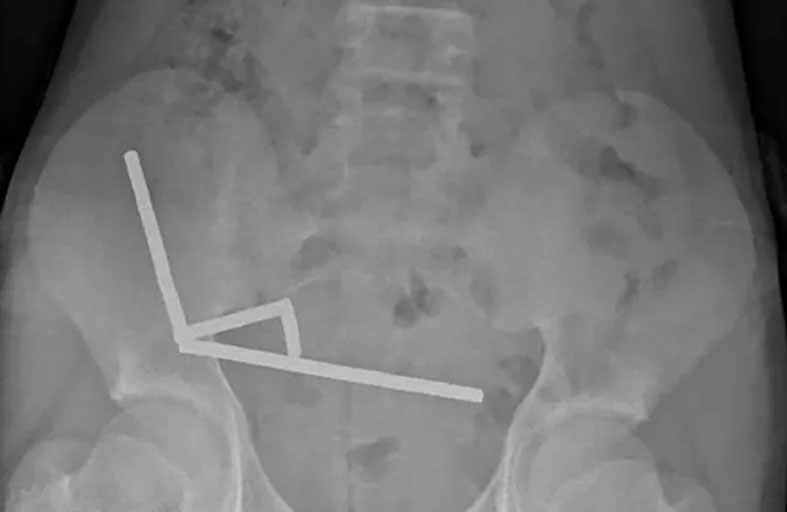

كشفت واقعة خطيرة في نيوزيلندا عن الوجه الآخر للتسوق الإلكتروني، بعدما ابتلع طفل يبلغ من العمر 13 عاماً نحو 100 مغناطيس صغير كان قد طلبها عبر الإنترنت، ما كاد يتسبب في كارثة صحية لولا التدخل الطبي السريع. ووفقاً لصحيفة "الغارديان" البريطانية، أُدخل الصبي إلى المستشفى بعد أربعة أيام من معاناته من آلام حادة في البطن، ليتبين لاحقاً أنه تناول المغناطيسات قبل أسبوع من ظهور الأعراض. وأظهرت صور الأشعة وجود أربع سلاسل من المغناطيس مرتبطة ببعضها، يصل عددها إلى ما بين 80 و100 قطعة من مغناطيس النيوديميوم القوي، بقياس 5×2 مليمتر، اشتراها الطفل من موقع "تيمو" حسب الصحيفة. وتلقى الطفل العلاج في مستشفى تاورانغا، حيث خضع لجراحة دقيقة لاستئصال المغناطيسات التي التصقت ببعضها داخل الأمعاء، مسببة خطراً كبيراً على حياته.